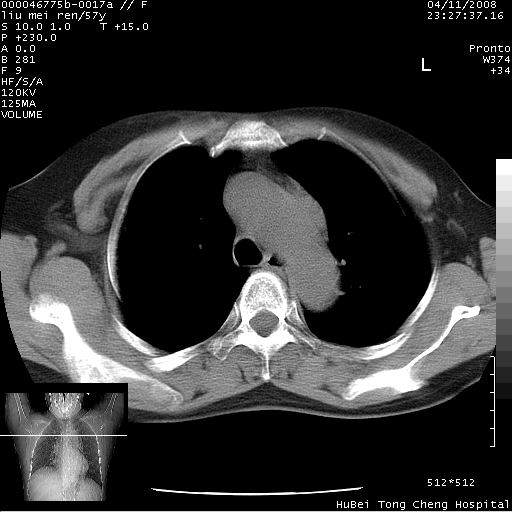

患者 女,57岁。因车祸受伤,其家属要求行“全身ct检查”。平素健康。

胸部ct轴位平扫(层厚10mm,螺距1.5,重建间隔10mm),图像如下:

上腔静脉变异,增强检查更全面一些。

左位上腔静脉,先天变异。